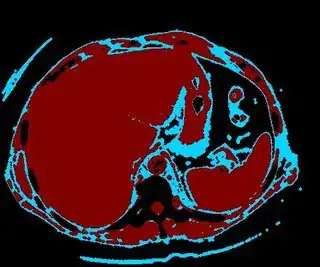

Below are some of the opened and segmented images. Of course there's more to be done in terms of

- separating out the liver region

- generalizing this to a large dataset

but hope this is at least a starting point.

You might be able to narrow down the region or interest by filtering out the darkest and the lightest regions from the segmented image. For this, use the k-means cluster centers, check for the extreme values (max and min) and remove the corresponding k values from the labeled image. Then you can look for large structures to the left of the result image. Worst case, you might get a hole on the left side when the extreme region filtering goes wrong. I've updated the code and results.